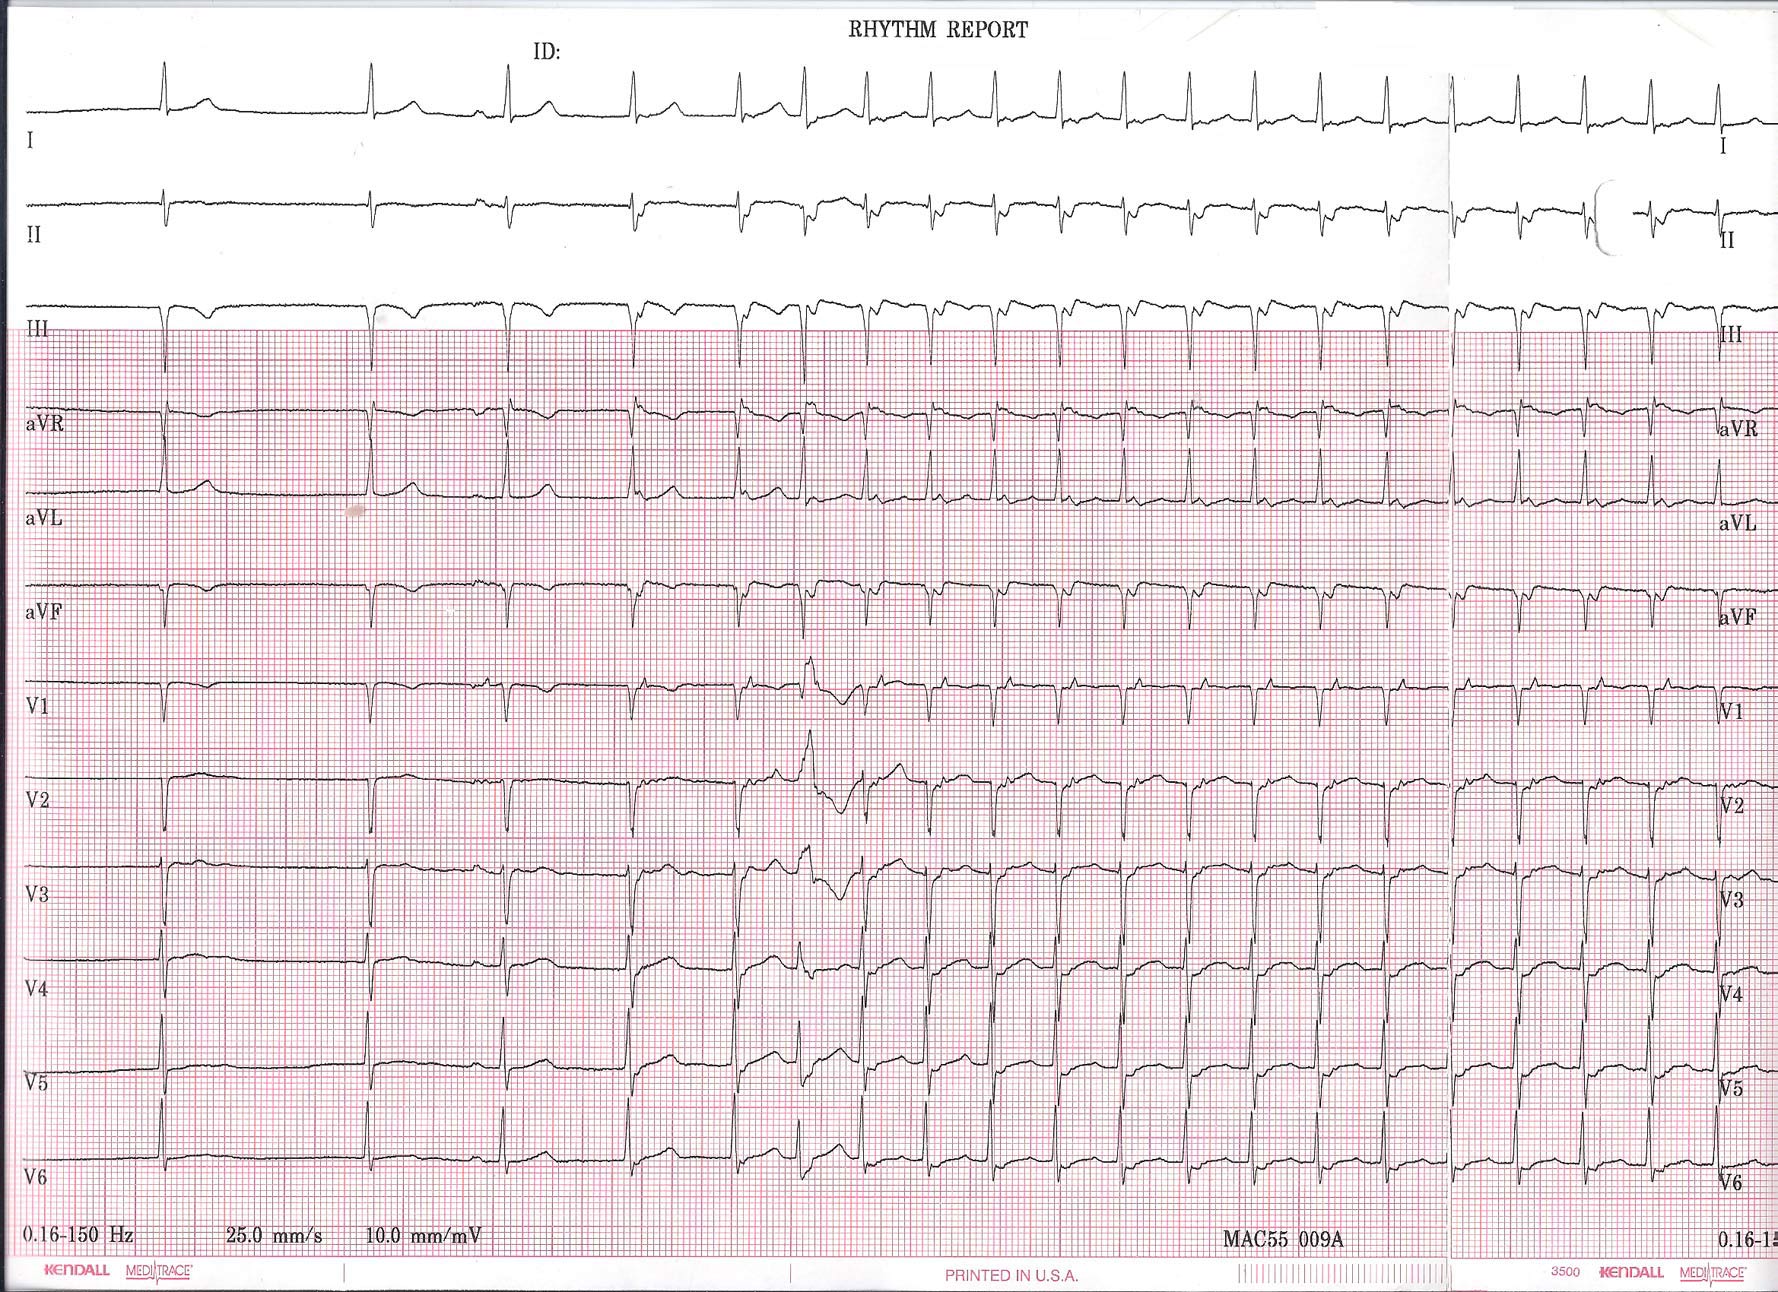

EKG Du Jour #25 - The Exercise Enthusiast

He was a 65 year-old previously healthy avid exercise enthusiast on no medications who was referred for evaluation of two near-syncopal episodes. The first episode occurred approximately 10 minutes after he stopped exercising on a treadmill. He felt he had to grab the wall to prevent himself from falling.

The second occurred after riding his bike home from the gym. Just after riding his bike home, he became very lightheaded and felt he had to sit on his front porch and nearly lost consciousness. His symptoms passed after resting for about 20 minutes.

While having his blood pressure checked, the nurse noted an irregular pulse. He felt fine and was unaware of his heart rhythm. A 12-lead rhythm strip was obtained and two representative 12-lead rhythm strips from the recording are shown below:

Click image to enlarge

Any ideas? What therapy (therapies?) would you recommend?